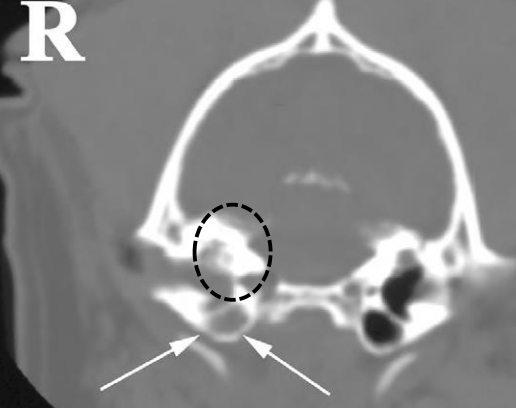

왼쪽 tympanic cavity 는 정상 / 오른쪽은 꽉 막혀 있고, 뼈도 없음.

오른쪽은 중이로 넘어가기 전에 빨리 조치 필요 / 왼쪽은 중이까지 이미 진행 / 동그라미는 petrous temporal bone; lysis가 일어나 개통성 있는 것처럼 보임 - 종양 의심